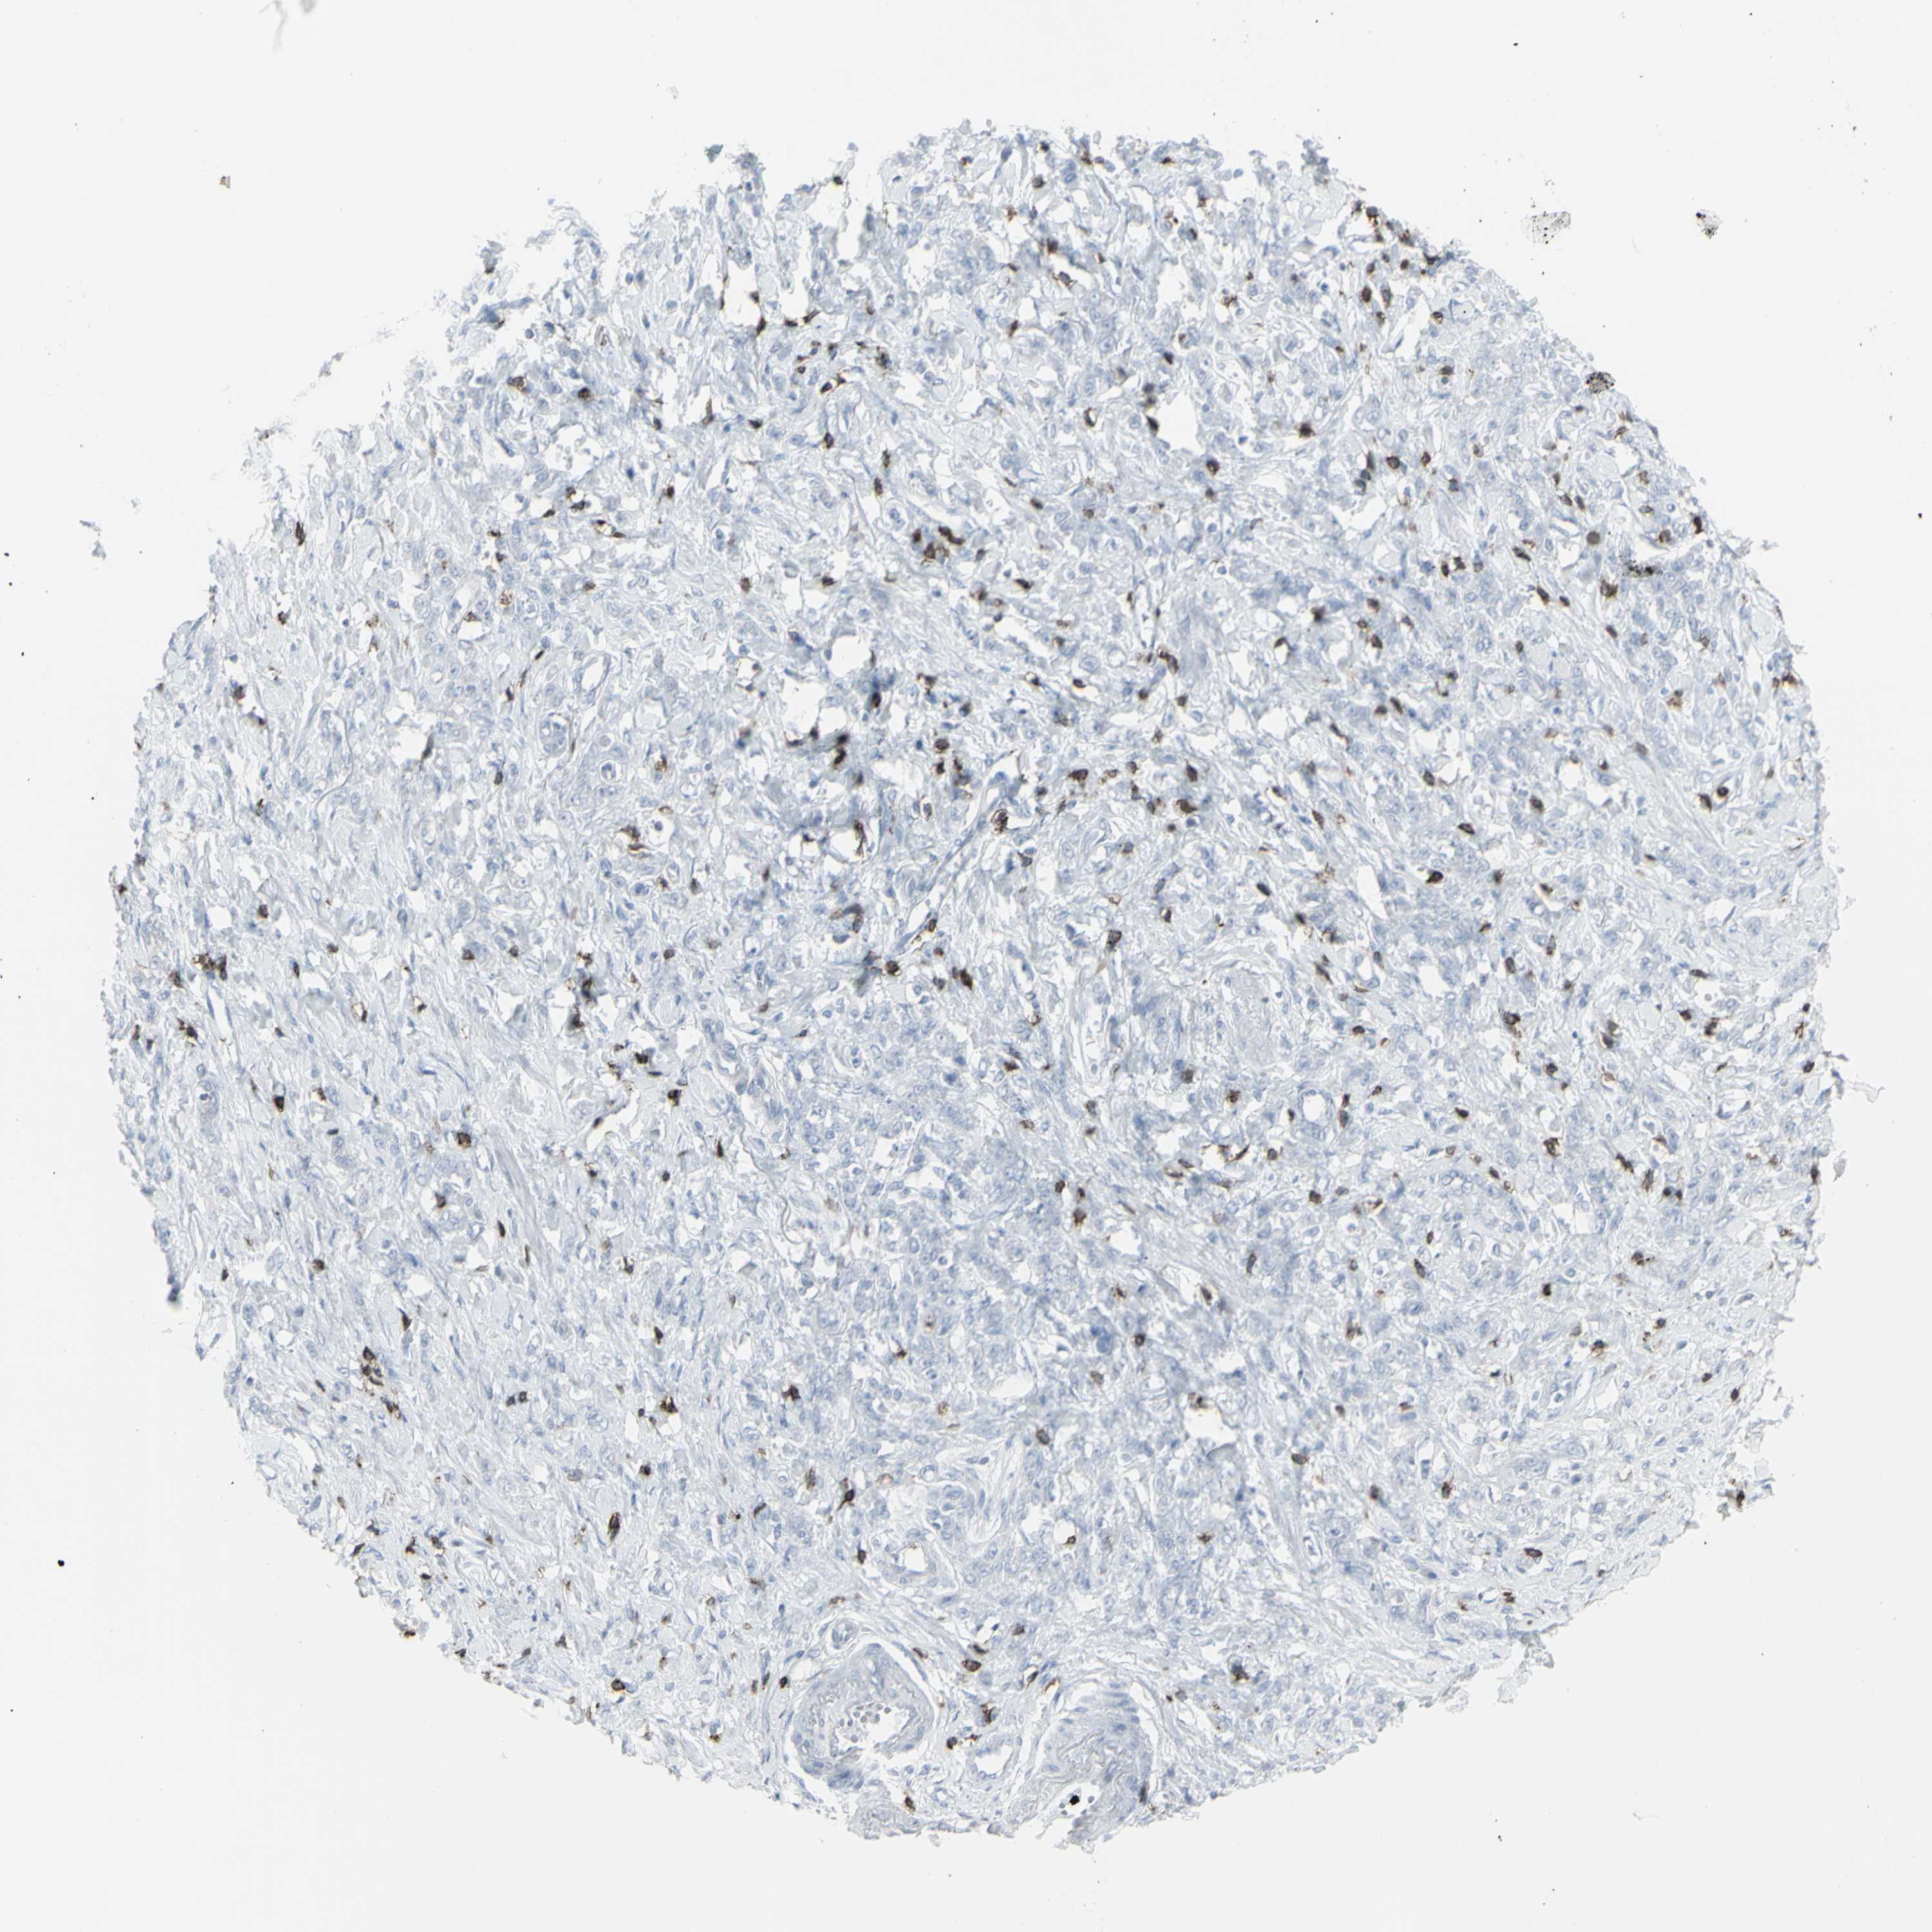

STOMACH CANCER - Protein expressioni

A mouse-over function shows sample information and annotation data. Click on an image to view it in a full screen mode. Samples can be filtered based on level of antibody staining by selecting one or several of the following categories: high, medium, low and not detected. The assay and annotation is described here.

Note that samples used for immunohistochemistry by the Human Protein Atlas do not correspond to samples in the TCGA dataset.

Antibody stainingi

Antibody staining in the annotated cell types in the current human tissue is reported as not detected, low, medium, or high, based on conventional immunohistochemistry profiling in selected tissues. This score is based on the combination of the staining intensity and fraction of stained cells.

Each image is clickable and will lead to virtual microscopy that enables deeper exploration of all samples and also displays staining intensity scores, fraction scores and subcellular localization as well as patient and tissue information for each sample.

Antibody HPA008750

Antibody CAB004651

Staining

High

Medium

Low

Not detected

Intensity

Strong

Moderate

Weak

Negative

Quantity

>75%

75%-25%

<25%

None

Location

Nuclear

Cytoplasmic/membranous

Cytoplasmic/membranous,nuclear

Adenocarcinoma, NOS

Adenocarcinoma, High grade